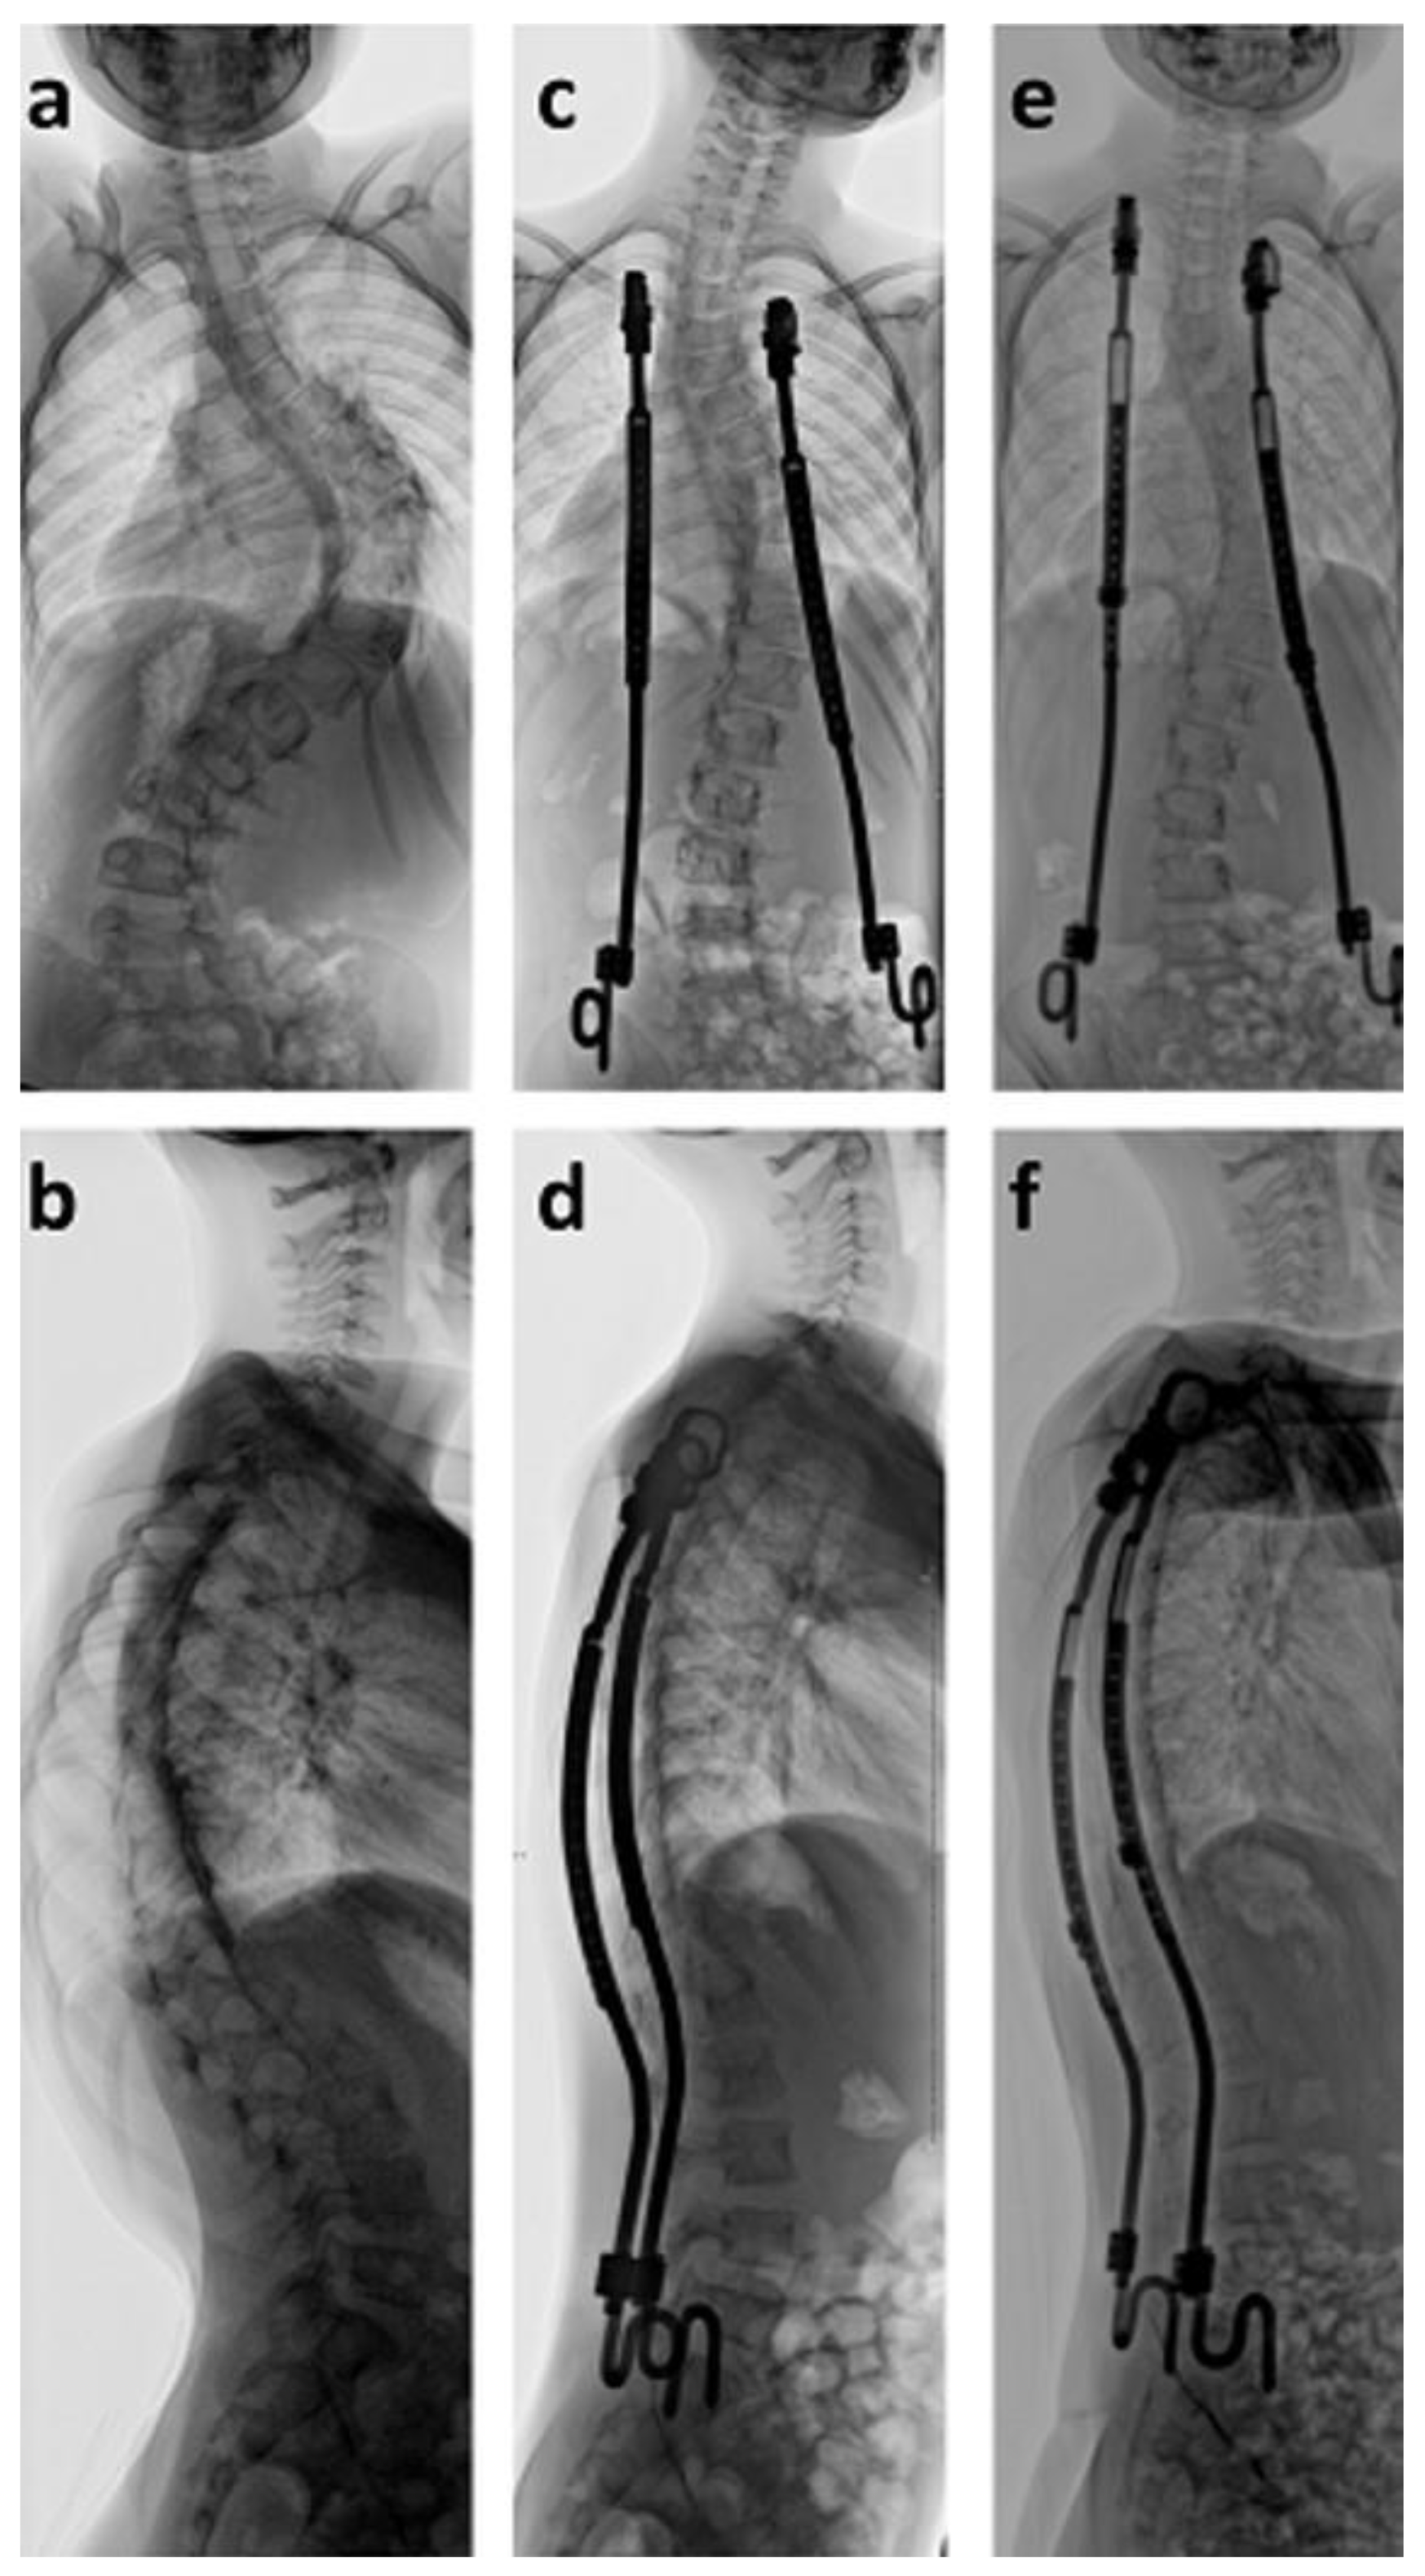

Figure 5. Fifteen-year old girl with juxta-spinal neurofibromatosis and severe three-dimensional upper thoracic spinal deformity (ac). MRI prior to surgical treatment revealed severe neurofibromatosis with thoracic obstruction, which was incompletely removed.

After radiological investigation, spinal deformity was divided into scoliosis, kyphosis, and lordosis. Each quantification of curves was done using the Cobb angle [30]. Scoliosis was defined as not existent (curve angle < 10°), mild (10–20°), moderate (21–40°), and severe (>40°). Thoracic kyphosis and lumbar lordosis are highly variable in children and are age dependent [14]. Values that were graded as pathological and were additionally quantified were those that were beyond the normal range of variation [14], i.e. above 40°, and those where abnormal curve patterns occurred such as kyphosis within the lumbar region. Radiographic evaluations were performed using standing or sitting a.p. (anterior posterior), lateral radiographs (Figure 5), MRI, or computed tomography (CT) scans if needed.